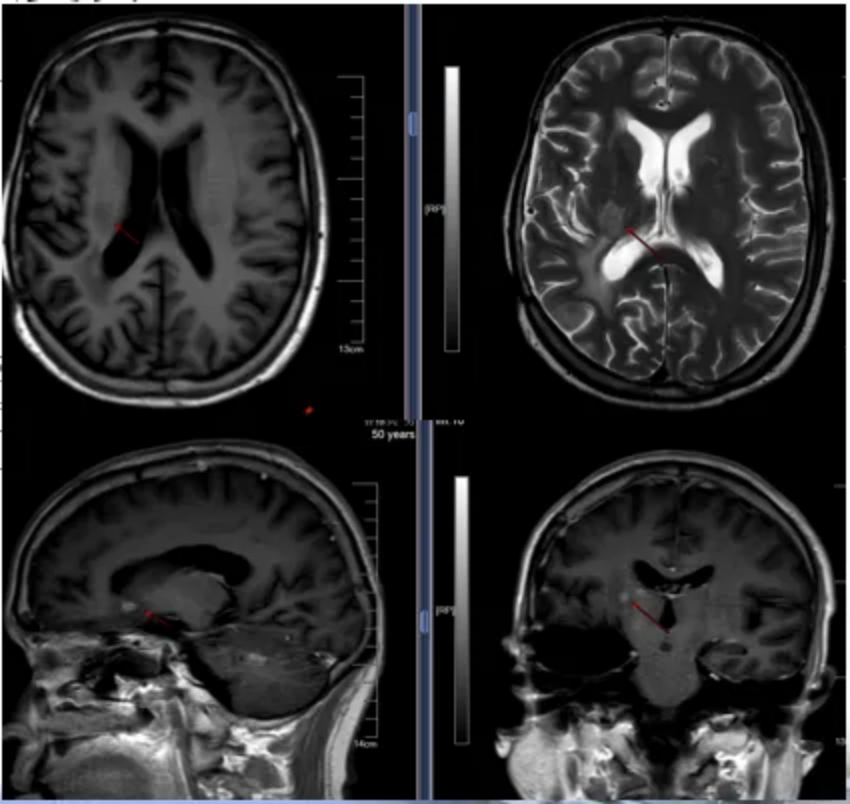

2020-12-12影像辅助检查:颅脑MRI增强+MRA+MRV+MRS,提示右侧颞叶可见类圆形不均匀T1等低信号,T2等高信号,DWI信号混杂,实性成分呈高信号,ADC呈等信号,大小约56mm*41mm*41mm,增强扫描呈不均匀显著强化,内见血管穿行(图1)。诊断:右侧颞叶占位,考虑淋巴瘤可能,结合临床;MRA可见病灶小血管穿行;颅脑MRV未见明显异常。

图1 颅脑MRI图像